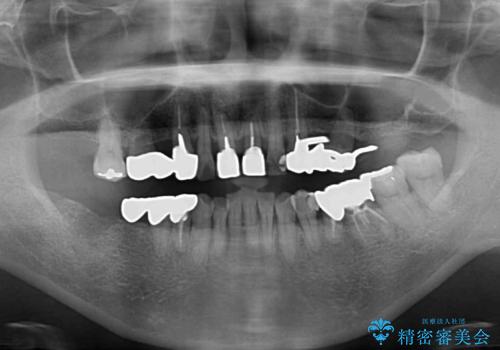

まずは抜歯が必要な歯を抜歯した上で仮歯に置き換え、インプラント埋入や歯周外科処置、根管治療を行うこととしました。

歯肉の状態が落ち着いた後に下顎の矯正治療を行い、その後補綴治療を行うこととしました。

インプラントに対する恐怖心が強く、欠損補綴は極力ブリッジを採用し、インプラントの数は必要最小限としました。